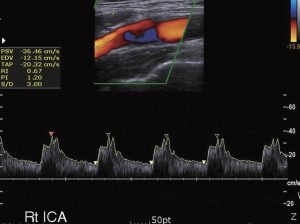

Karotis ve vertebral arterlerin renkli Doppleri

Beyne oksijenli kan taşıyan boynun ana arterlerini değerlendirmek için kullanılır. Bazen, bu hayati arterler plak oluşumu nedeniyle daralabilir. Damarların daralması felç riskini artırabilir.

Karotis ve vertebral arter renkli Doppler taramasının amacı, boynunuzdaki beyninize kan akışını sağlayan arterler olan karotid ve vertebral arterlerde ateroskleroz (plak nedeniyle daralma) varlığını tespit etmektir. Karotis arter renkli Doppler incelemesi için bazı endikasyonlar uzuvlarda güçsüzlük, felç veya işlev bozukluğu, konuşmada değişiklik, görme bozuklukları, uzuvlarda uyuşma veya karıncalanma ve denge bozukluklarını içerir. Doktorunuz steteskopuyla boynunuzdaki kan akışını dinlerken bir uğultu (ses veya üfürüm) tespit ederse, karotis renkli Doppler taraması isteyebilir.